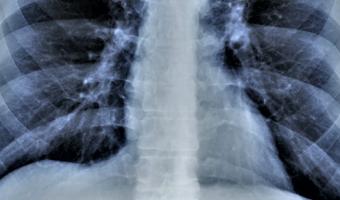

Unterstützung für Ihre Lungengesundheit Auf Mehr Luft erwarten Sie spannende, von Expert:innen aufbereitete Informationen und aktuelle Beiträge, die Ihre Lungengesundheit nachhaltig verbessern. Bild Bild was ist Asthma Bild was ist COPD Bild was ist Alpha-1 Bild Was ist Cystische Fibrose Bild Die Lunge - ein lebenswichtiges Organ - Etwa 300 Millionen stark durchblutete Lungenbläschen sorgen für den lebensnotwendigen Austausch zwischen Sauerstoff und Kohlendioxid. Funktionen der Lunge Wissenswertes für Sie News Rauchfreie Gastronomie: Was bringt es? COPD COPD-Patiententyp: Chronischer Bronchitiker Asthma COPD Sport Sport im Winter mit Asthma und COPD Allgemein Wann Ihr Kind mit Husten zum Arzt sollte Ernährung Warum Sie auf gutes Essen nicht verzichten müssen? Rauchentwöhnung Rauchfrei in 10 Schritten Asthma COPD Freizeit Reisen Die perfekten Reiseziele für den Herbst Asthma COPD Berufswahl für Einsteiger und Umsteiger Mehr Artikel Expertentipps Unsere spannenden Umfrageergebnisse werden von Top-Expert:innen diskutiert und besprochen. ZU DEN TIPPS Bild Richtig inhalieren Ein Inhalator kann bei einem Asthmaanfall Leben retten - allerdings nur, wenn er richtig benutzt wird. VIDEO Bild Asthma Notfall Richtiges Verhalten bei einem Asthma Notfall beugt Ängste vor und ist von zentraler Bedeutung. Notfallplan Bild Genie hilft Hier finden Sie weiterführende Links zu Informationen Ihrer wichtigsten Fragestellungen. Zum Genie Bild ZurückWeiter Newsletter Jetzt zum Newsletter anmelden und laufend informiert bleiben! Vorname Nachname E-Mail Zustimmung zur Verarbeitung personenbezogener Daten Ich stimme zu, dass meine personenbezogenen Daten - wie in der Datenschutz-Richtlinie beschrieben - zur Zusendung und Analyse der E-Mailings verarbeitet werden. Diese Zustimmung kann ich jederzeit mit Wirkung für die Zukunft widerrufen. *Pflichtfeld Bitte dieses Feld leer lassen Bild Finde uns jetzt auch auf Social Media! Abonniere uns auf Facebook, Instagram oder LinkedIn für aktuelle News und Infos. Mehr-Luft.at @mehrluft.at Mehr-Luft.at